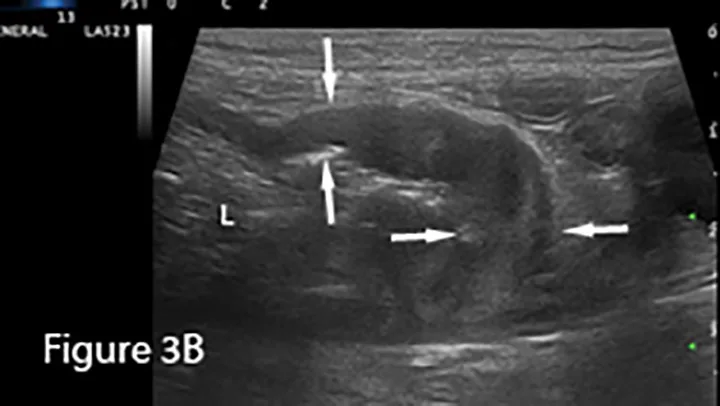

Focal loss of wall layering and eccentric thickening of the intestinal wall (arrows) are present on ultrasound image showing abnormally dilated small intestinal lumen (L) orad to the mass. Normal empty small intestinal segments are seen in the transverse section in the near field (*). Surgery confirmed diagnosis of mucinous adenocarcinoma.